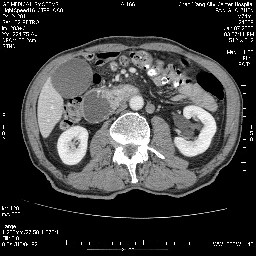

病变主要位于钩突(癌)。如是壶腹部,肝内外胆管扩张明显。

病变考虑为钩突癌。

十二指肠降段扩张,水平段狭窄成鼠尾状,肠壁明显增厚,胰腺勾突增大成不均匀强化,其内可见低密度区,胆囊增大,1十二指肠水平段腺癌侵犯胰腺勾突可能大,2胰腺癌侵犯十二指肠(只有胆囊增大没有肝内外胆管扩张不好解释)代除外.

十二指肠降段扩张,水平段狭窄成鼠尾状,肠壁明显增厚,胰腺勾突增大成不均匀强化,其内可见低密度区,胆囊增大,1十二指肠水平段腺癌侵犯胰腺勾突可能大,2胰腺癌侵犯十二指肠 。

今日手术结果:胰腺钩突癌侵犯十二直肠,腹腔淋巴结转移.